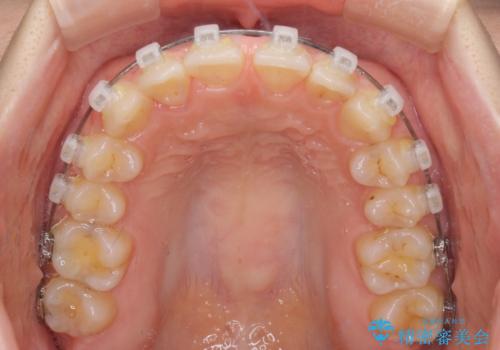

- クリアブラケット

- 前歯の隙間やクロスバイトを気にして来院された患者様です。

結婚式の予定があり、可能であれば結婚式までに治療を終えたいとのことで、短期間で治療をおける可能性の高いワイヤー装置にて矯正治療を行うこととしました。

ギリギリとなりましたが、結婚式直前にワイヤー装置を外すことができました。

ワイヤー装置除去後に細かい部分を短期間のマウスピース矯正にて仕上げました。